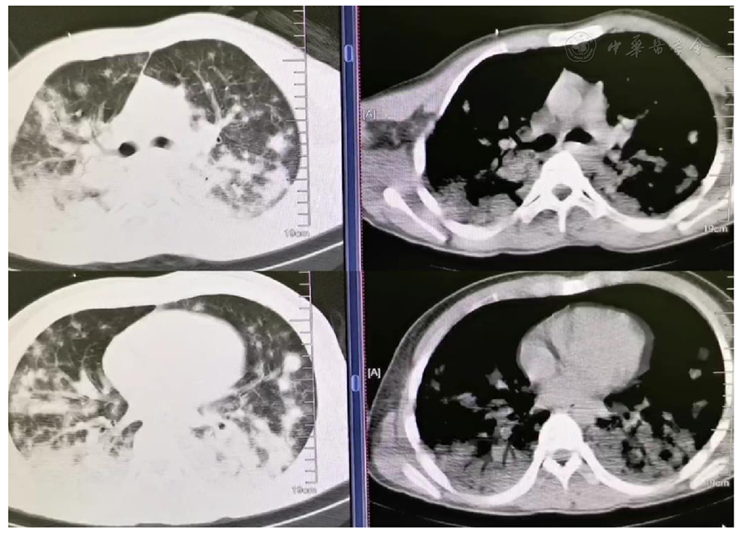

2.胸部CT(3月21日):

双肺多发结节、片结、片状密度增高影伴斑片状渗出,多考虑感染性病变,血源性可能(图1)。

图1 患者入院第1天胸部CT表现

原发性肺NK/T细胞淋巴瘤的影像学表现缺乏特异性,很难与肺炎、肺结核、肺癌相鉴别,容易造成诊断及治疗不及时。CT检查时常可以发现肺部病变,包括双肺大片实变及浸润影,软组织肿块影,结节影,磨玻璃影,单侧或双侧肺不张、胸腔积液,有时可累及支气管,可能伴有肺门或纵隔淋巴结肿大[8,9]。本例患者的CT检查在早期便为我们提供了重要线索,肺部多发病灶,沿血管走行分布,提示血源性感染可能,肝脾肿大,腹腔及腹膜后淋巴结肿大,皮下脂肪层软组织结节。经验性抗感染治疗效果不佳,事后反思肺部病变应该是来源于淋巴管,并没有影响到肺泡通气血流比值,所以在患者肺部病变持续进展时,肺部氧合情况一直不错,出现病变与生理变化不相符。